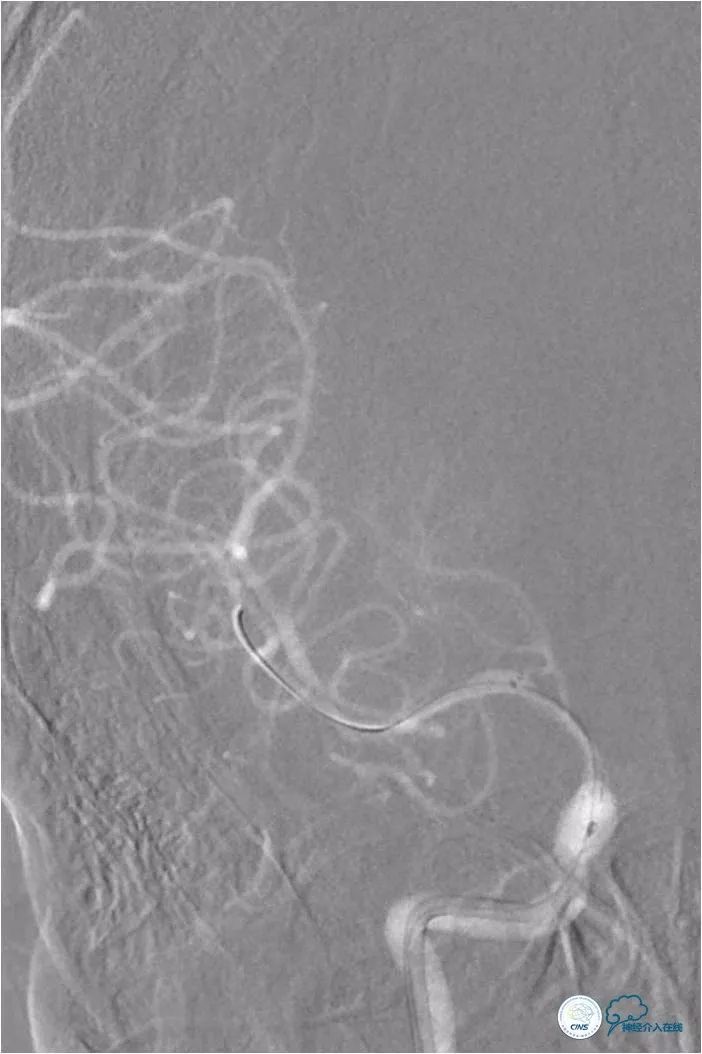

路径图下将Transend微导丝(0.014″,300cm)至右大脑中动脉M3段,沿微导丝送入Gateway球囊(2.0mm×15mm)于狭窄处扩张(图7)。

图7

撤出球囊导管,后沿微导丝送入Wingspan自膨式支架(3.0mm×15mm),期间将导引导管送至右颈内动脉C3段,以增加系统支撑力(图8)。

图8